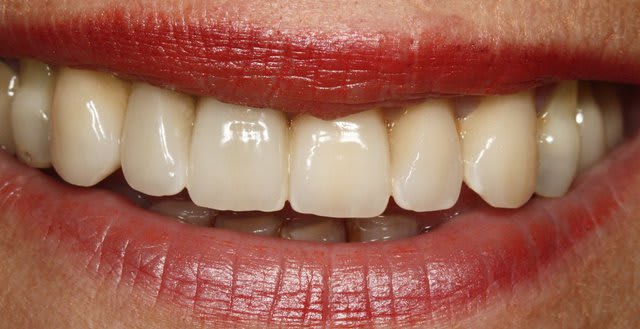

Gros point positif ici: la patiente semble avoir une hygiène impeccable et dégage assez peu les collets au sourire, d'où une certaine facilité à gérer l'esthétique "rose".

Bonne chance, il y a ici moyen de transfigurer le sourire de la dame.

Dis moi tu lui as dis quoi pour prendre la photo n°2 (avec la langue) :))))